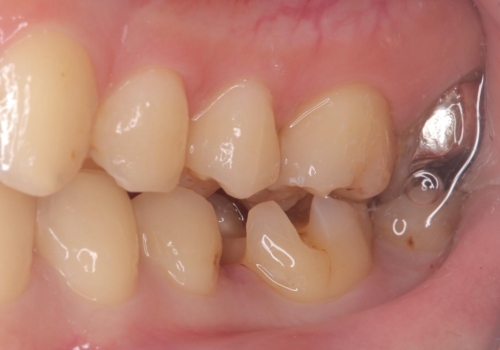

- 主訴:銀の詰め物が取れた、奥の銀の詰め物も一緒に白くしたい

保険適用のメタルインレーの脱離で来院されました。審美性、適合性、清掃性の観点から2本ともセラミックインレーでのやり替えとなりました。